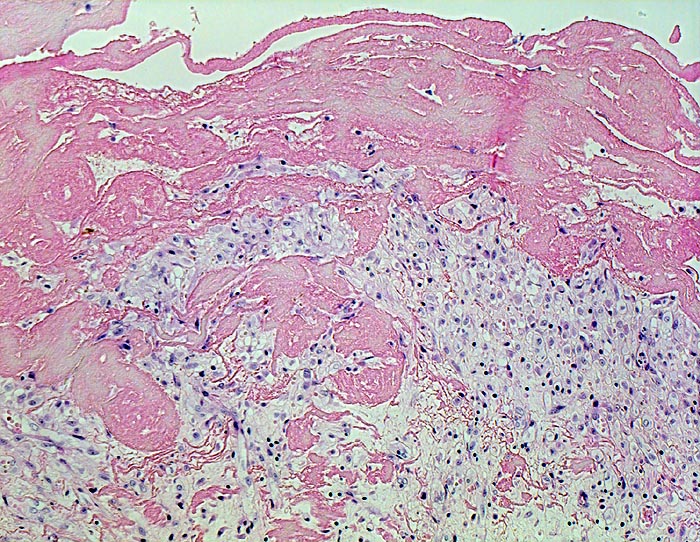

PathoPic ID 4534 - fibrinöse Perikarditis

fibrinöse Perikarditis

Ein Teil des

Fibrins liegt dem Epikard auf, ein

Teil ist bereits inkorporiert in das organisierende Granulationsgewebe.

Patientin verstorben in Urämie.

Histologie

100